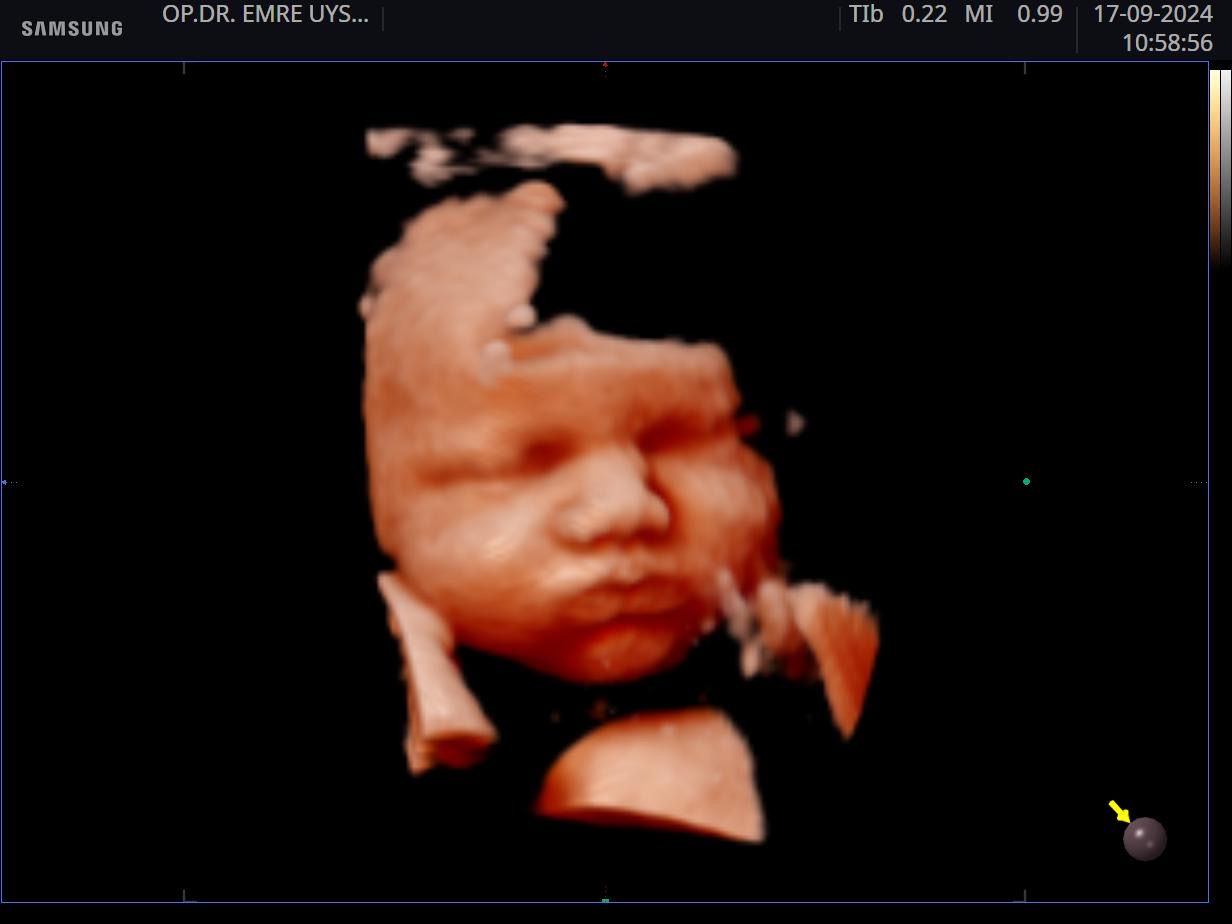

Her kadının hayatında önemli dönüm noktaları vardır. Hiç şüphesizki hamilelik süreci ve doğum bunlardan en kıymetlisidir. Biz de bu değerin farkındayız ve 15 yılı aşan tecrübemiz ile minik mucizenize sağlıkla kavuşma yolculuğunda sizin yanınızdayız. 4d ultrason ile bebeğinizin sağlığını yakından takip ederken, klinik takibimiz ile de süreci eğlenceli ve sağlıklı bir şekilde geçirmeniz için elimizden gelenin en iyisini yapıyor olacağız. Yaşasın Hamilesiniz!